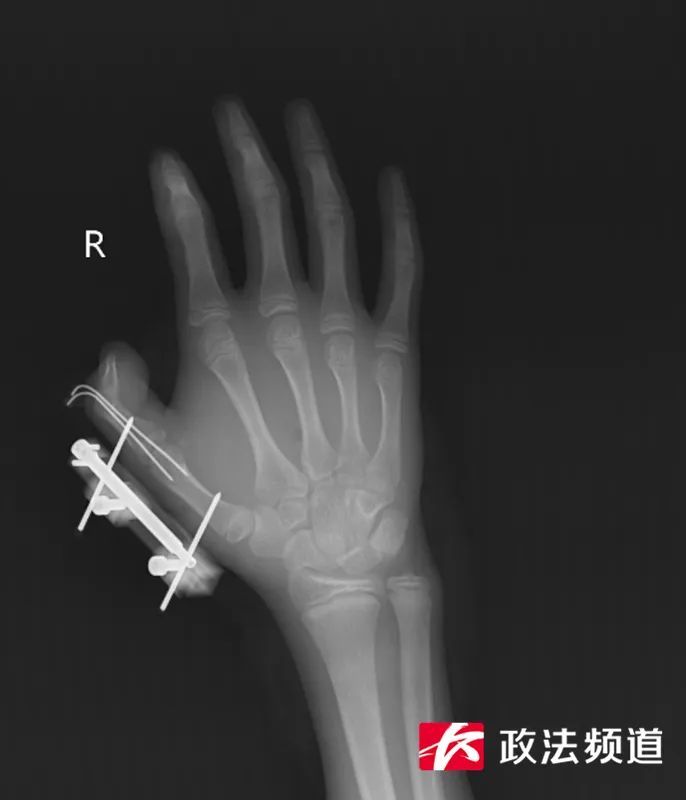

接诊的医生发现,维维右手拇指虎口撕开一道约10cm的伤口,伤口深可见骨、肌肉组织断裂外露,同时伴有拇指骨折、关节脱位,拇指已完全失去知觉。手足显微外科团队立即为他开通绿色通道,急诊手术清创、复位脱位的拇指掌指关节、固定骨折、逐层修复肌肉,术后经过医护团队7天的精心护理,维维的拇指虽然保住了,但需持续进行康复训练恢复手部精细动作功能。